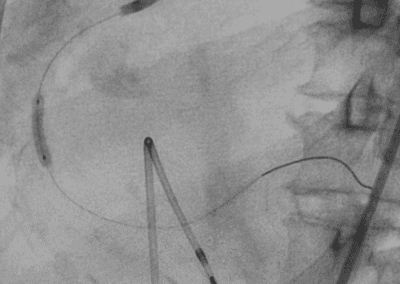

- Angioplastica: Un intervento minimamente invasivo per dilatare le arterie ristrette, ripristinando il flusso sanguigno.

- Bypass arterioso: Nei casi più gravi, un intervento chirurgico per creare una nuova via per il flusso sanguigno, bypassando le arterie ostruite.